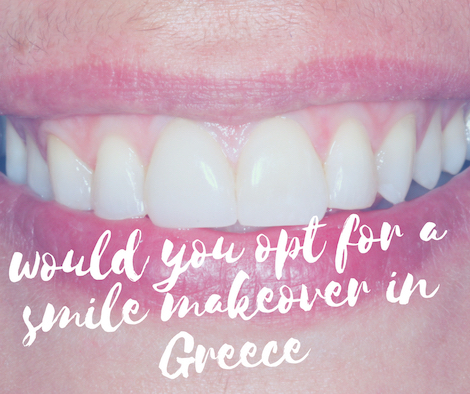

Teeth erosion, is the loss of tooth substance from chemical causes.

The responsible chemical causes are usually acids, initially causing damage to the enamel and in advanced stages, damage to the dentin as well.

In the oral cavity, acids are usually the result of frequent vomiting from eating disorder or acid reflux.

Acids can be induced in the oral cavity from external causes too. Carbonated soft drinks and energy drinks or acidic fruits ,when consumed in large quantities can prove catastrophic.